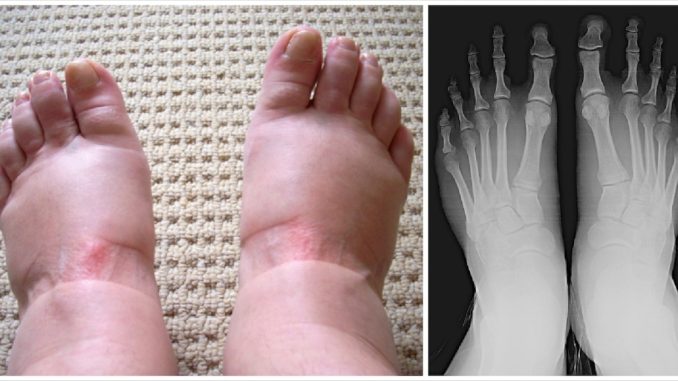

7. Gout

Gout is a form of arthritis caused by the buildup of uric acid crystals in the joints. The National Institute of Arthritis and Musculoskeletal and Skin Diseases (NIAMS) explains that gout attacks often occur suddenly, causing intense pain, redness, and swelling—especially in the big toe.

Gout can be managed through diet, hydration, and prescribed medications that lower uric acid levels. If you experience severe or recurrent episodes, talk to your doctor about long-term management strategies.